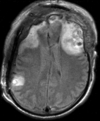

Within Exam:

Exam 1 PD aligned to T1